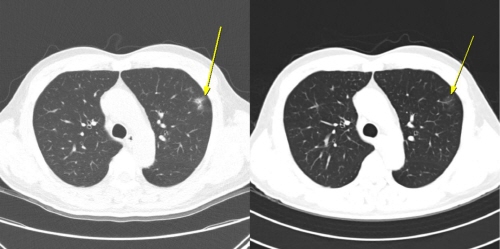

연구팀은 치료 중 나타난 이상반응 양상에 따라 환자를 ▲이상반응이 전혀 없는 ‘무이상반응군’ ▲임상 증상이나 혈액검사 이상을 동반한 ‘증상성 이상반응군(증상군)’ ▲증상은 없지만 CT에서 폐 주변부 미세 염증성 음영, 일시적 대장벽 비후, 장간막 염증, 반응성 림프절 종대 등 면역반응으로 해석되는 변화만 나타난 ‘무증상 영상 이상반응군(무증상 영상군)’으로 분류했다. 전체 198명 중 무증상 영상군은 12명, 증상군은 56명, 무이상반응군은 130명이었다.